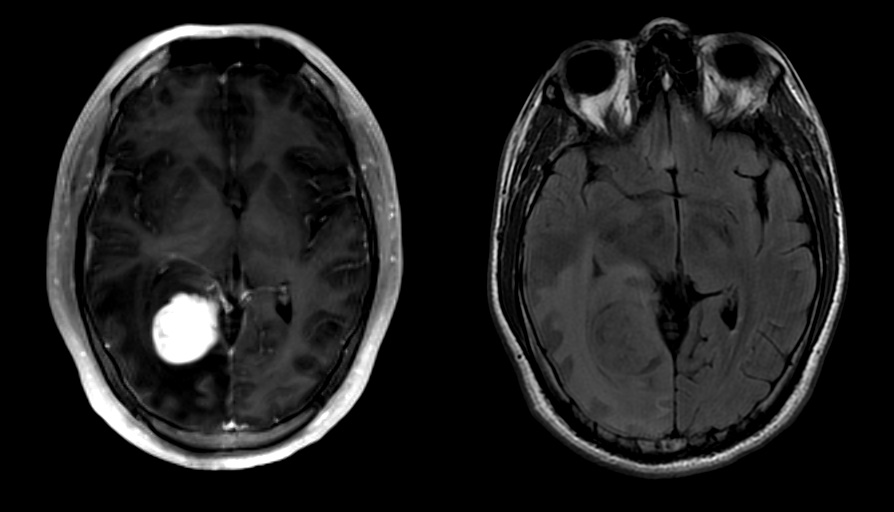

Radiology description

- Commonly discrete, well circumscribed mass with avid uniform contrast enhancement

- Hyperdense on computed tomography and T2 hyperintense on magnetic resonance imaging

- Reference: Childs Nerv Syst 2009;25:1203

Radiology images